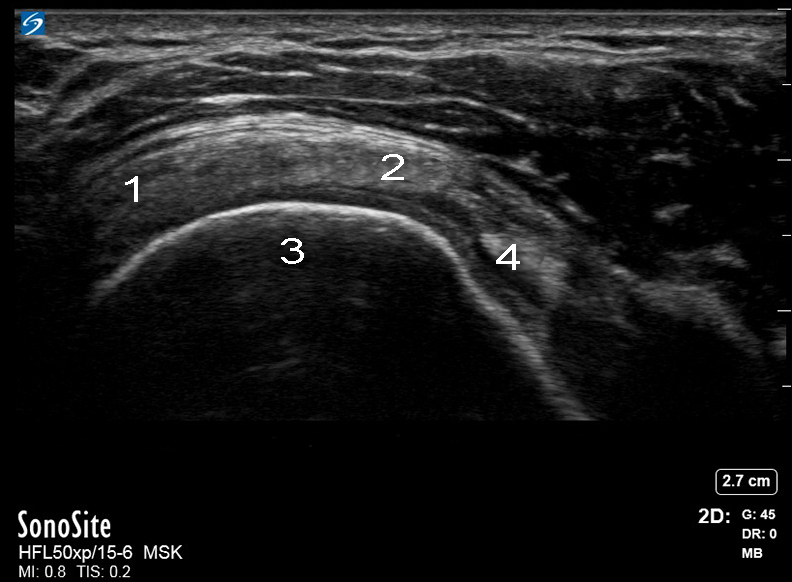

肩袖横轴图像

冈下肌

冈上肌

肱骨头

二头肌腱 (BT)